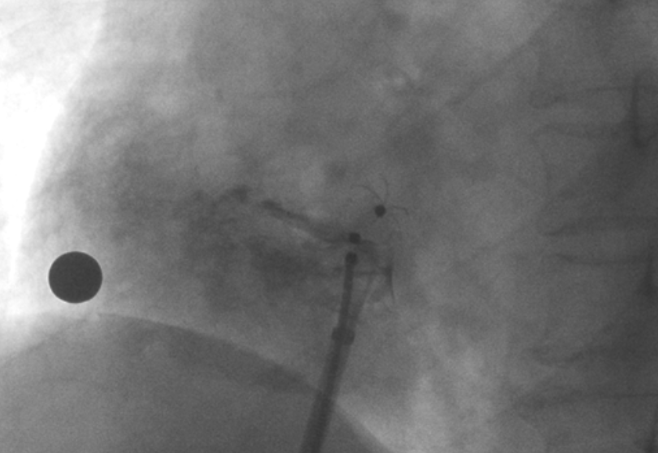

造影顯示PFO封堵完全,無殘余分流, 試驗器械充分舒展并貼合良好

術(shù)中造影顯示患者為PFO且長隧道型,目前市場上已商業(yè)化的PFO封堵器難以滿足該患者解剖結(jié)構(gòu)封堵需求。迪創(chuàng)醫(yī)療自主研發(fā)的OmniSeal PFO封堵器自適應(yīng)性雙盤貼合設(shè)計能廣泛適應(yīng)不同PFO隧道長度的解剖結(jié)構(gòu)和形態(tài),其雙盤外包覆式阻流和隧道內(nèi)填充阻流相結(jié)合的雙重阻流設(shè)計,可為此患者實現(xiàn)有效封堵。與此同時,OmniSeal首創(chuàng)的完全可穿刺式設(shè)計,也為此患者最大程度地保留了房間隔區(qū)域穿刺通道,以實現(xiàn)全兼容未來可能的左心系統(tǒng)二次介入術(shù)。術(shù)終造影和心臟超聲顯示封堵完全、效果良好。作為OmniSeal的首例臨床應(yīng)用,本次手術(shù)的順利完成和優(yōu)異效果充分體現(xiàn)了產(chǎn)品的設(shè)計創(chuàng)新優(yōu)勢。